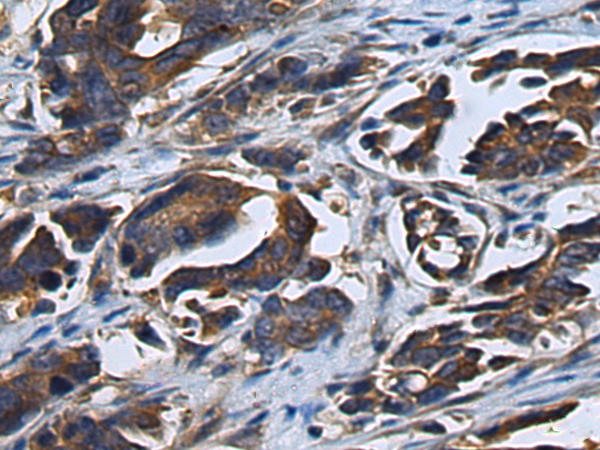

ELISA, IHC |

IHC positive control: |

Human colorectal cancer |

IHC Recommend dilution: |

100-300 |